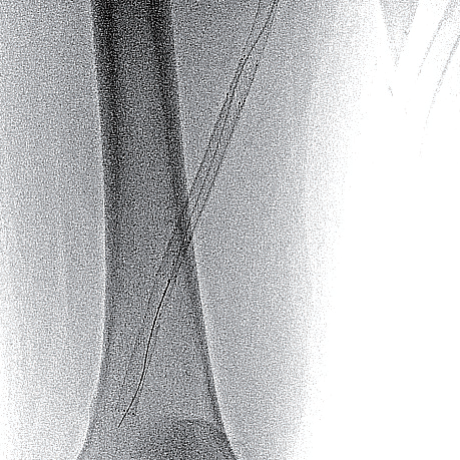

- ステント近位端は非常に硬化しており、0.014 inch wireでのknuckle wiringおよび0.035 inch wire のtail 側でもステント内へ進入できず

- 4 Fr IMA造影カテーテルにマイクロカテーテル併用下でtapered coil typeの0.018 inch wireにてなんとかステント近位端を通過(図2)